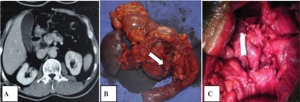

病例学习:小肠类癌一例

基本病史:男性,63岁,伴有潮红和腹泻症状。行CT及PET/CT检查,结果如下:影像特点 CT检查结果显示在右侧肠系膜见一个边界不清的,其内不均质,边缘有毛刺的肿块,内可见点状钙化。邻近小肠的结缔组织增生反应,与病 ...